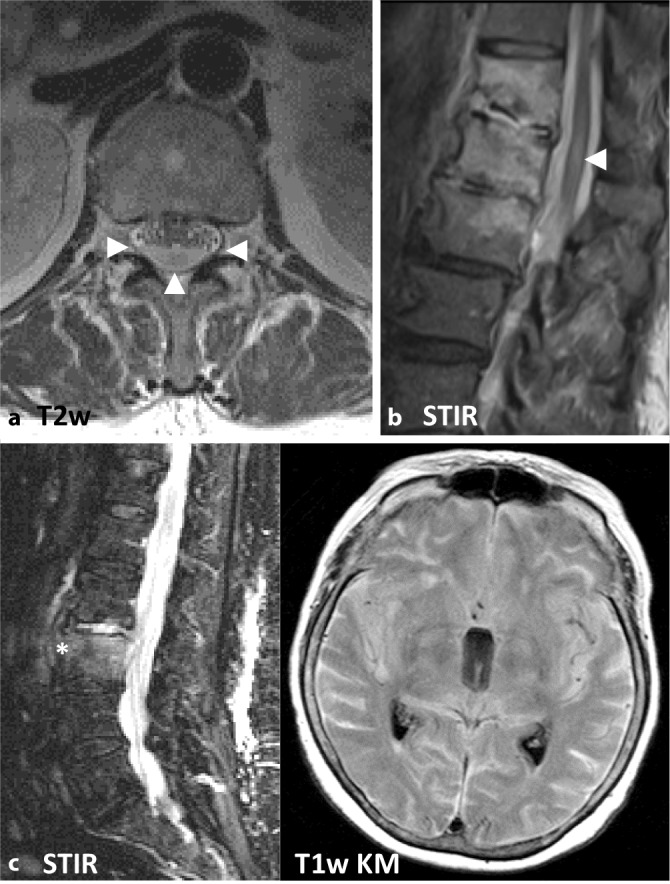

Unabhängig vom Alter kann es anschließend zu einer Ausbreitung des Infektionsgeschehens nach paravertebral, subdural und epidural kommen [2]. Hierbei sind als weitere Komplikationen, neben einer paravertebralen bzw. epiduralen Abszedierung, subdurale Abszesse sowie eine Ausbreitung in das zentrale Nervensystem möglich, beispielsweise in Form einer Meningitis, Myelitis oder Enzephalitis (Abb. 1; [4]).

Die MRT ist mit einer Sensitivität von 96 %, einer Spezifität von 92 % und einer Genauigkeit von 94 % die Bildgebung der Wahl [4]. Noch vor knöchernen Destruktionen zeigt sich eine Zunahme des Flüssigkeitssignals der betroffenen Wirbelkörper und Bandscheiben im Sinne eines T1w-hypointensen, T2w-hyperintensen Ödems sowie in den T1-gewichteten Sequenzen eine Anreicherung von i.v.-Kontrastmittel (Abb. 2). Der Verlust des sog. „nuclear cleft sign“, einer T2w-Hypointensität der zentralen Bandscheibe, die von einigen als altersabhängig physiologischer Prozess, von anderen als erster Grad der Degeneration der Bandscheibe gewertet wird, kann mit einer Spondylodiszitis einhergehen, ist für eine solche jedoch nicht spezifisch [14].